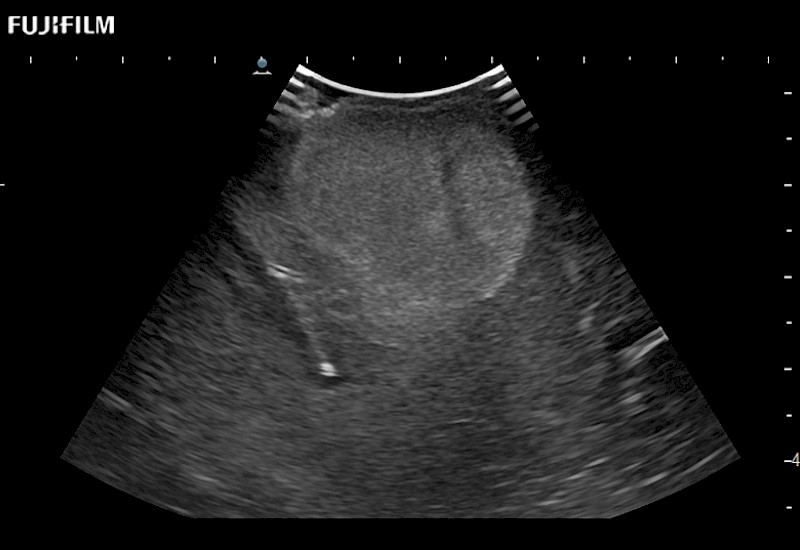

The world's only phased array burr-hole transducer that is ideal for scanning during burr-hole guidance procedures.

Main Specifications: